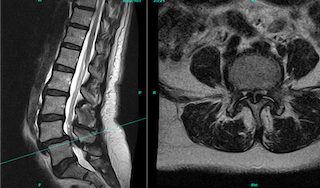

MRI scans showing a side view and a cross-section of the lumbar spine and lower back pelvis area.

When should TLIF be considered?

TLIF surgery may be appropriate when:

• Non-surgical treatments have not provided enough relief

• Nerve compression causes persistent leg pain or weakness

• Spinal instability contributes to symptoms

• Imaging confirms conditions such as spondylolisthesis or degenerative disc disease

When performed for the right indication, TLIF can significantly improve function and quality of life.